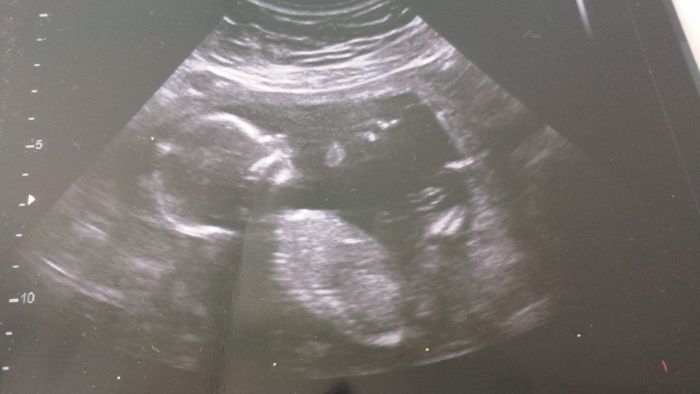

Dnes jsem 16+1 a prcek ma bez nozicek 10 cm, snad se foto vlozi.

Povedlo se, nohy ma natazene pred sebou, proto uz citim asi pohyby, se roztahuje jako tatínek